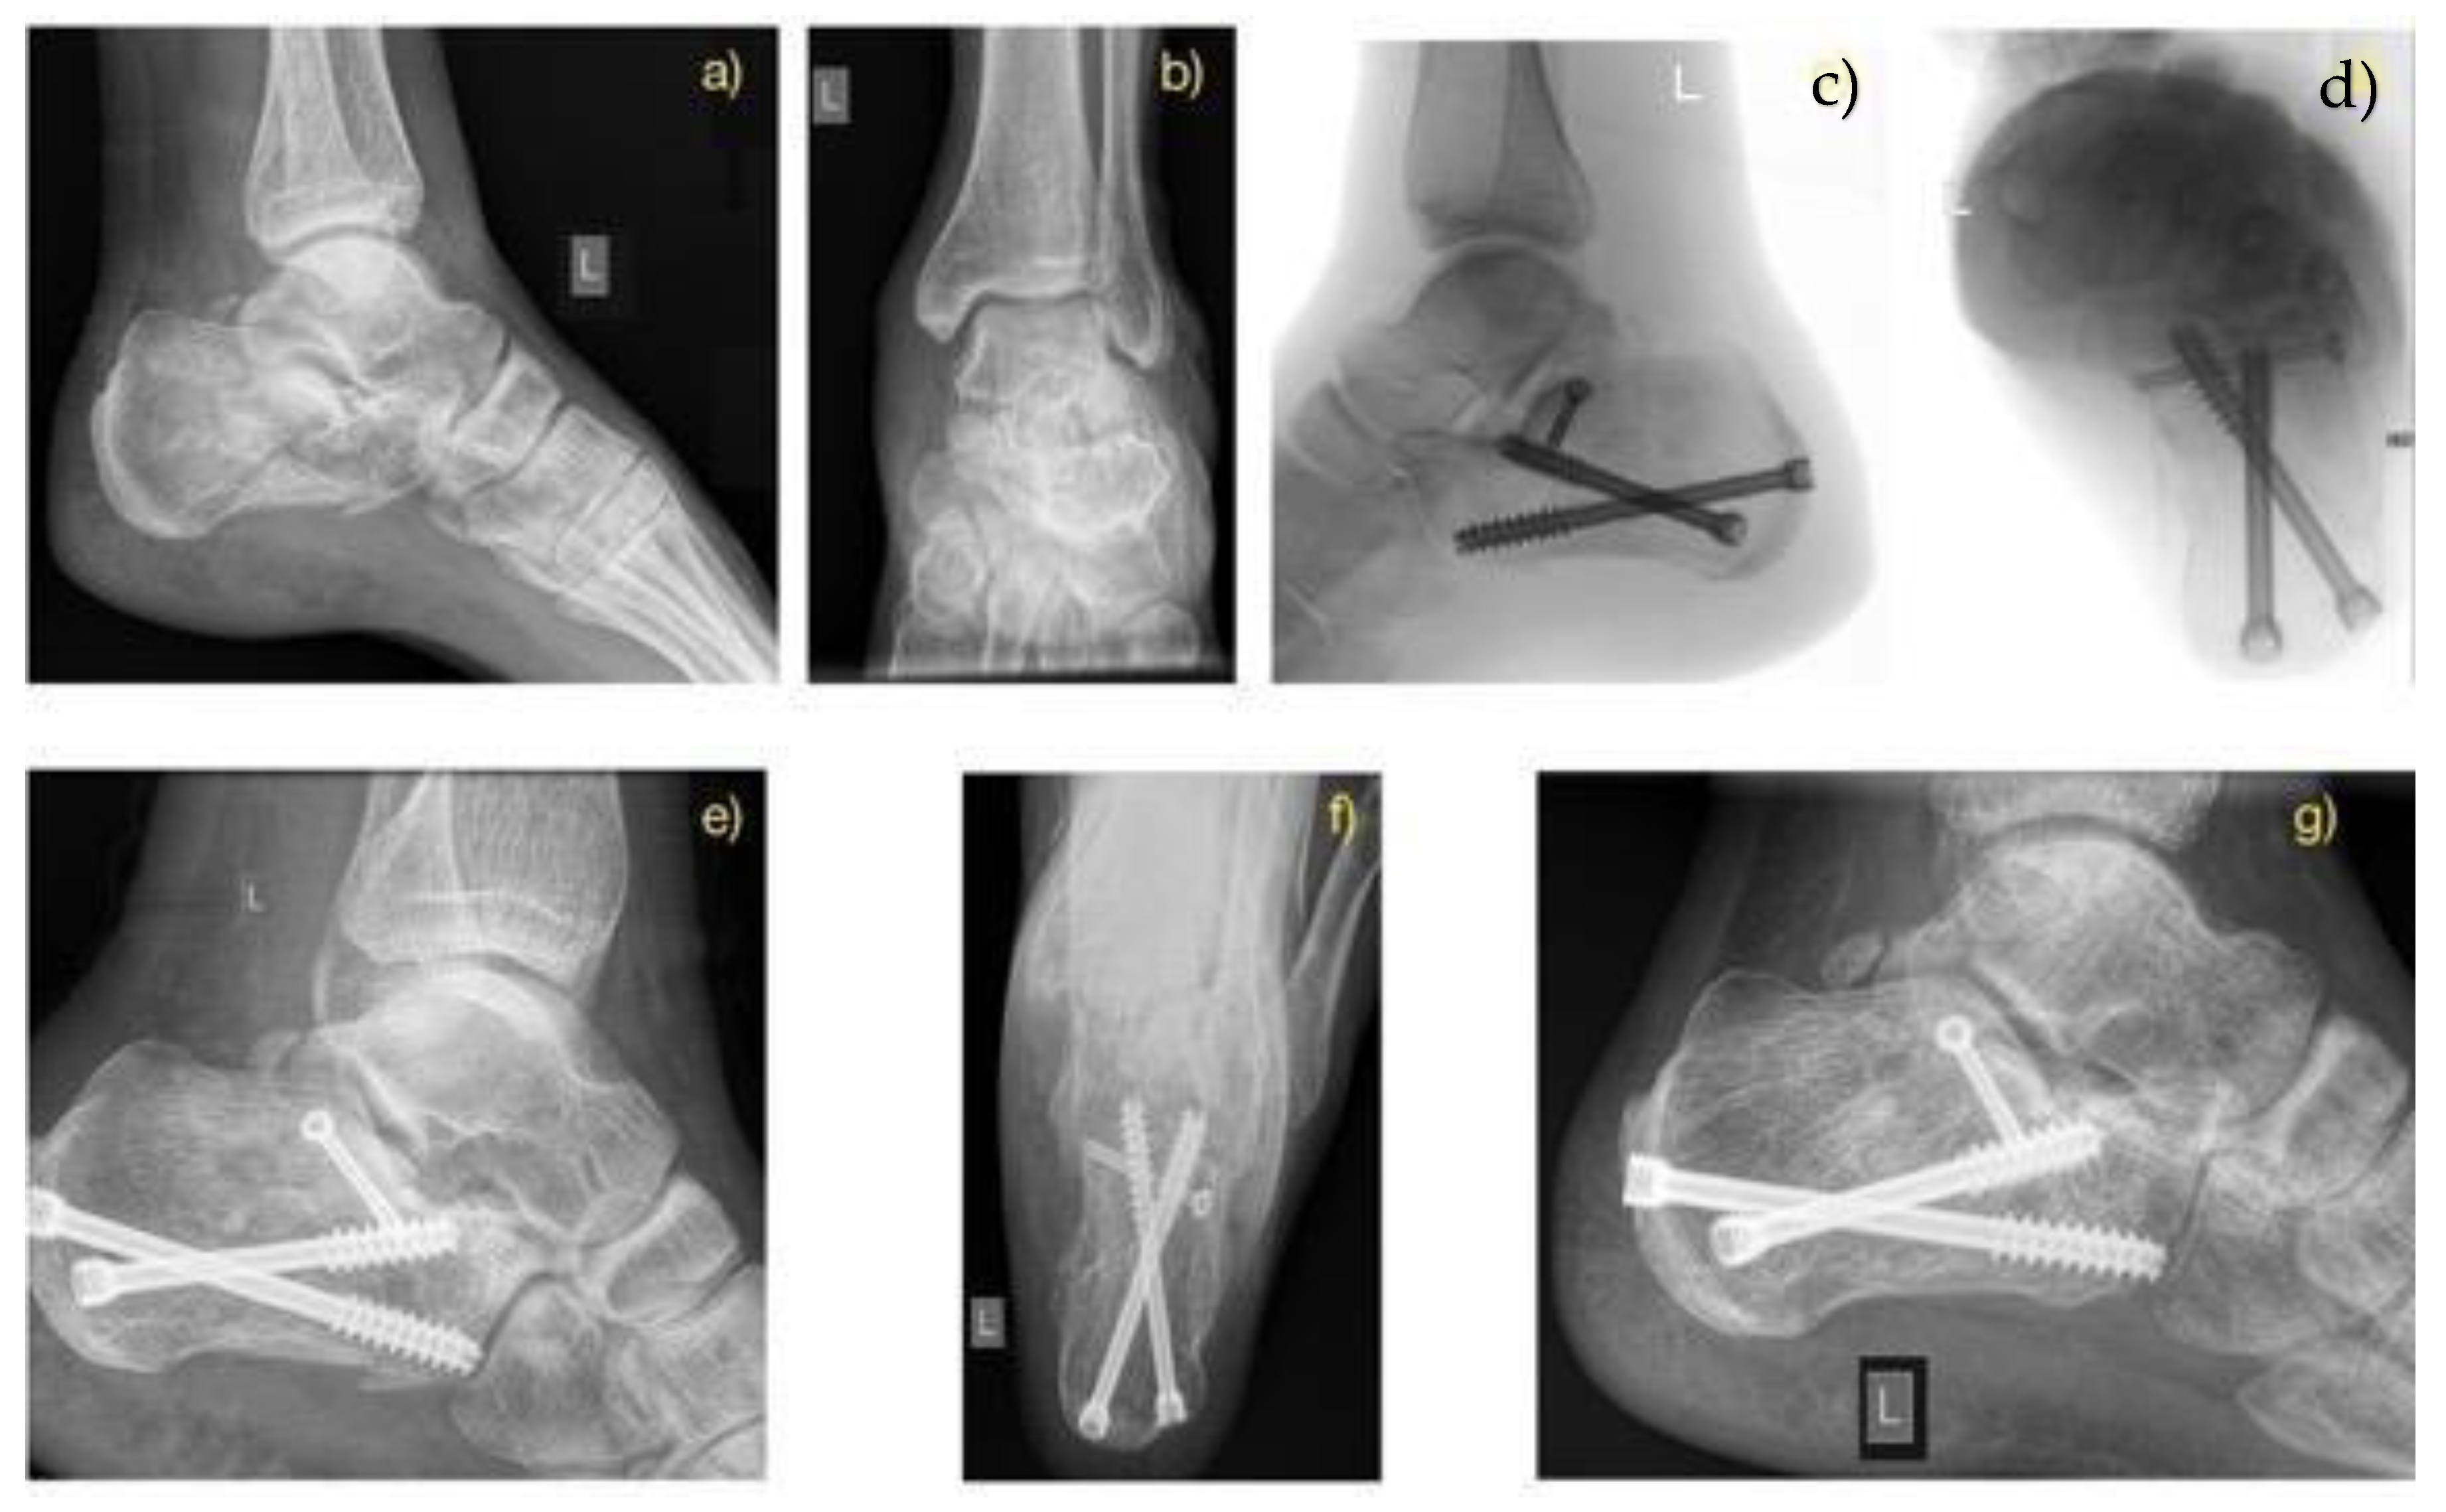

2.2. Treatment Methods